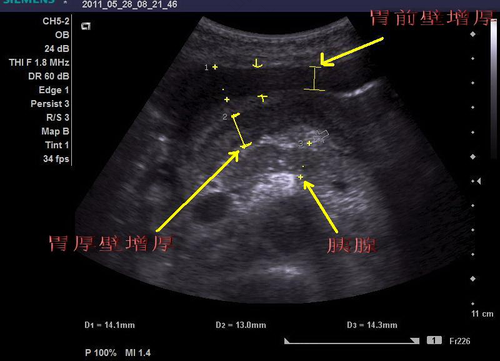

进行b超检查可以检查出部分胃部疾病,并不是所有的胃病都能通过b超检查出来。如果患有胃溃疡、胃肿瘤等病症,是能够通过腹部b超进行诊断的,这就可以知道患病的位置以及具体病情如何。